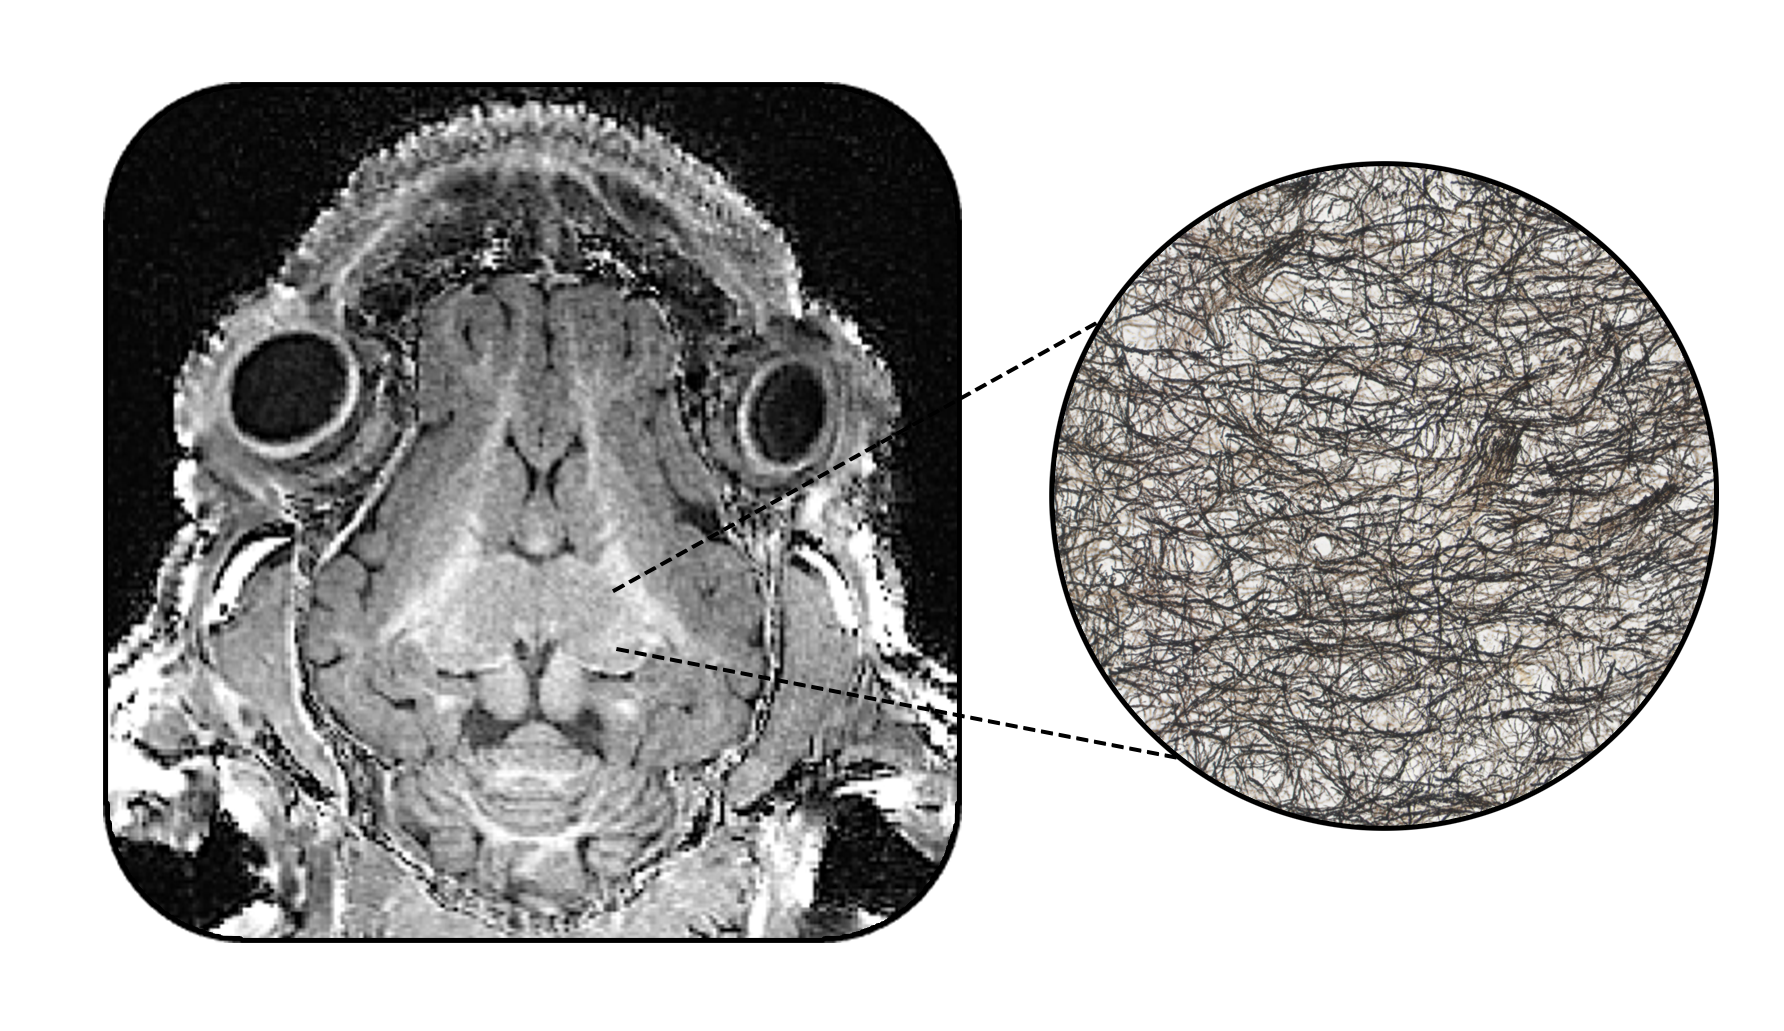

With over 1,000 individual MRI scans of the pig brain performed since 2010, our lab is well versed in multimodal imaging across multiple ages and field strengths (3T and 7T).

A DEEPER DIVE

What are MRI images telling us? Are scans truly reflective of biology?

To answer this, our lab paired multimodal neuroimaging together with histology to get

a deeper look into the brain.